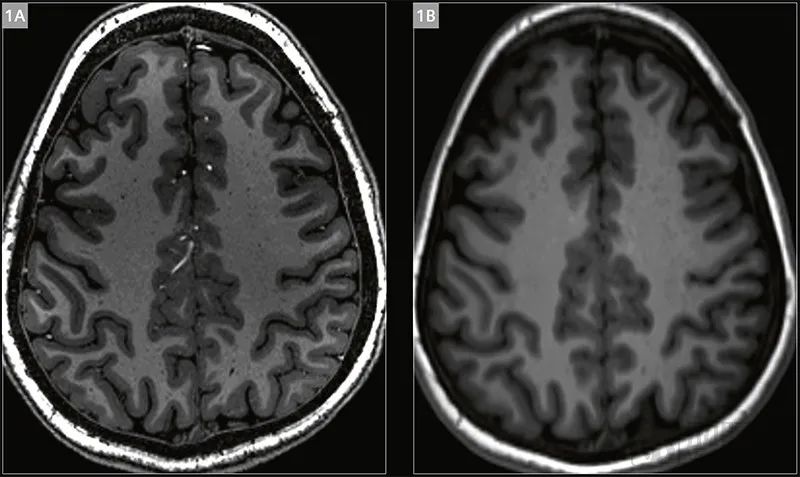

图片7T(上图左)与3T(上图右)脑部图像对比

更大的场强通常意味着可以更高的图像分辨率或更快的人体成像,比如3T磁共振图像可以分辨1mm细节,到了7T,则可以实现0.5mm精细成像,远比3T和临床主流的1.5T图像清晰,甚至可以看到人类大脑神经元传导信息的图像。以癫痫为例,与3T相比,7T磁共振能额外发现43%的癫痫病灶。在肌肉骨骼成像中,7T可以捕捉到软骨和半月板中的最小细节,从而支持医生做出治疗决策。